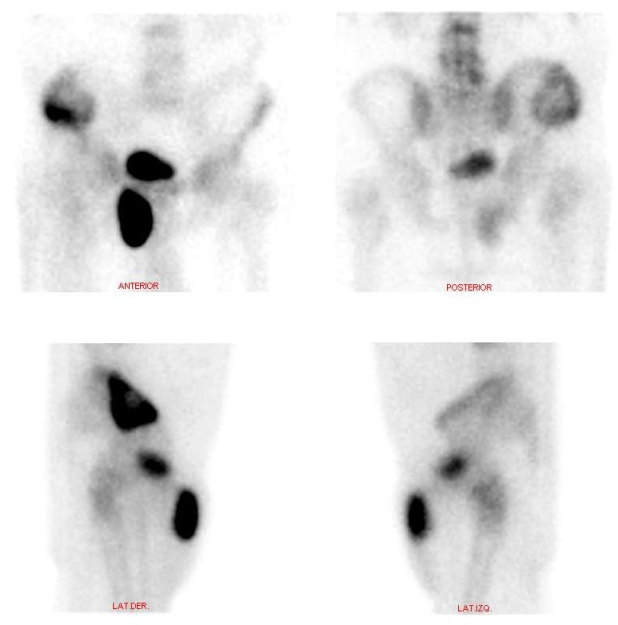

Se presenta el caso de un paciente masculino de 70 años con un único antecedente de carcinoma basocelular invasivo previamente operado, al cual le es solicitado un centellograma óseo debido a una lesión en alerón ilíaco derecho reportada en una tomografía computarizada (TC) de pelvis. Se realiza rastreo de cuerpo completo con 99mTc-MDP, imágenes estáticas de pelvis y SPECT. En el estudio de cuerpo completo se observó lesión en cresta ilíaca derecha, hipercaptante con componente lítico central, junto con un foco de hipercaptación de intensidad similar a la vejiga, proyectado por debajo de la rama superior del pubis derecho, de aspecto sacular (fig. 1). En las imágenes segmentarias con vistas anteroposteriores y laterales se evidencia que el hallazgo es de ubicación anterior respecto a la rama isquiopubiana derecha (fig. 2). En el estudio SPECT se confirma una gran lesión hipermetabólica con área central fotopénica de aspecto redondeado, que protruye de la cresta iliaca derecha y no respeta bordes anatómicos. Además, se evidencia claramente la existencia de conexión entre la vejiga y la zona hipercaptante de aspecto sacular ya mencionada (figs. 3 y 4).